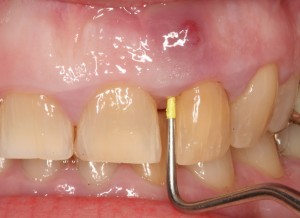

Μετά τη νέκρωση του πολφού και του νεύρου του δοντιού ο πόνος σταματάει δημιουργώντας την ψευδαίσθηση ότι το πρόβλημα ξεπεράστηκε. Η αποσύνθεση όμως των νεκρών ιστών προχωράει παράγοντας πύον το οποίο συσσωρεύεται και δημιουργεί ακρορριζικό απόστημα. Το απόστημα πιέζει το οστό της γνάθου που το περιβάλλει προκαλώντας οξύ πόνο . Η μόλυνση καταστρέφει το οστό γύρω από το απόστημα καθιστώντας δύσκολο να κρατηθεί το δόντι στη θέση, αλλά υπάρχει κίνδυνος να εξαπλωθεί και σε άλλα όργανα του σώματος δημιουργώντας σοβαρές επιπλοκές της υγείας.

- Δημιουργία συριγγίου στα ούλα

- Εκροή πύου